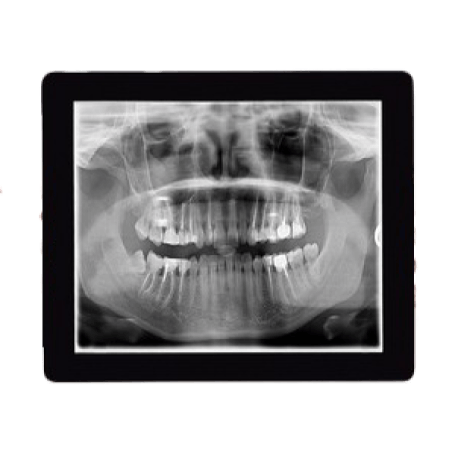

An excellent orthodontic clinic stands out through board-certified, experienced orthodontists, advanced technology like digital X-rays, convenient treatments, and a patient-first approach. The clinic should offer a free initial consultation, have a great office location, and prioritize crafting confident and healthy smiles through comprehensive care.

In orthodontics, new technologies like digital X-rays are utilized for safer and more accurate diagnostics. These advancements enhance treatment precision and patient comfort, ensuring a seamless orthodontic experience.